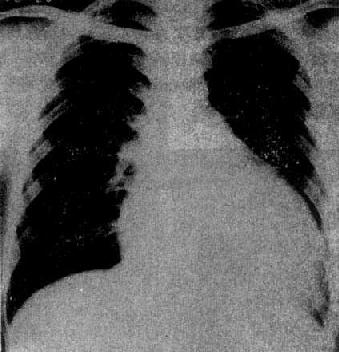

图3-2-17 慢性肺原性心脏病

心呈二尖瓣型,右心室增大,肺动脉突出,但无左心耳增大。肺动脉扩张,尤以右下肺动脉为明显,有肺门截断现象,说明有肺动脉高压。肺纹理增强,肺透明度增加,膈平而低,说明有慢性支气管炎和肺气肿

X线表现(图3-2-17)为肺动脉高压和肺部慢性病变的改变:①肺动脉高压,常出现于心形态改变前之前;②右心室增大,心呈二尖瓣型,心胸比率大于正常者不多,部分病例心比正常为小,与肺气肿、膈低位等因素有关。左心室如增大则常为心力衰竭所致。右心房增大少见,常由于右心室压力增高,右心房排血困难所致,右心房不增大;③肺部慢性病变,有慢性支气管炎,广泛肺组织纤维化及肺气肿等表现。